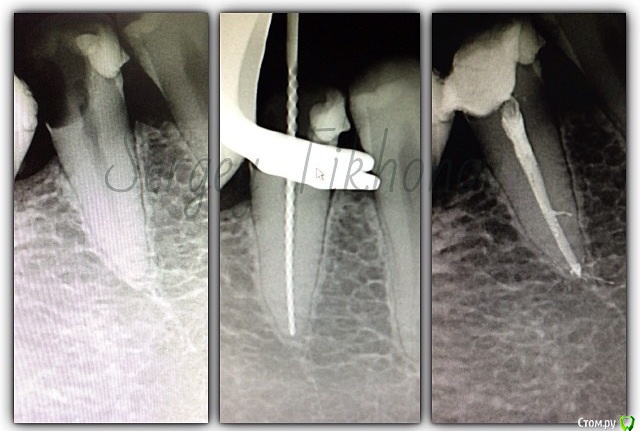

SSTi Опубликовано 21 января, 2015 Автор Поделиться Опубликовано 21 января, 2015 Легкий и приятный кейс. 46. Витальное эндо. Медиальные 35.04, дистальные 40.04. Дистальных 2. В конце инструментации ушла перегородка и они объединились в 1 протяженный щелевидный канал. Латералка. 7 Ссылка на комментарий